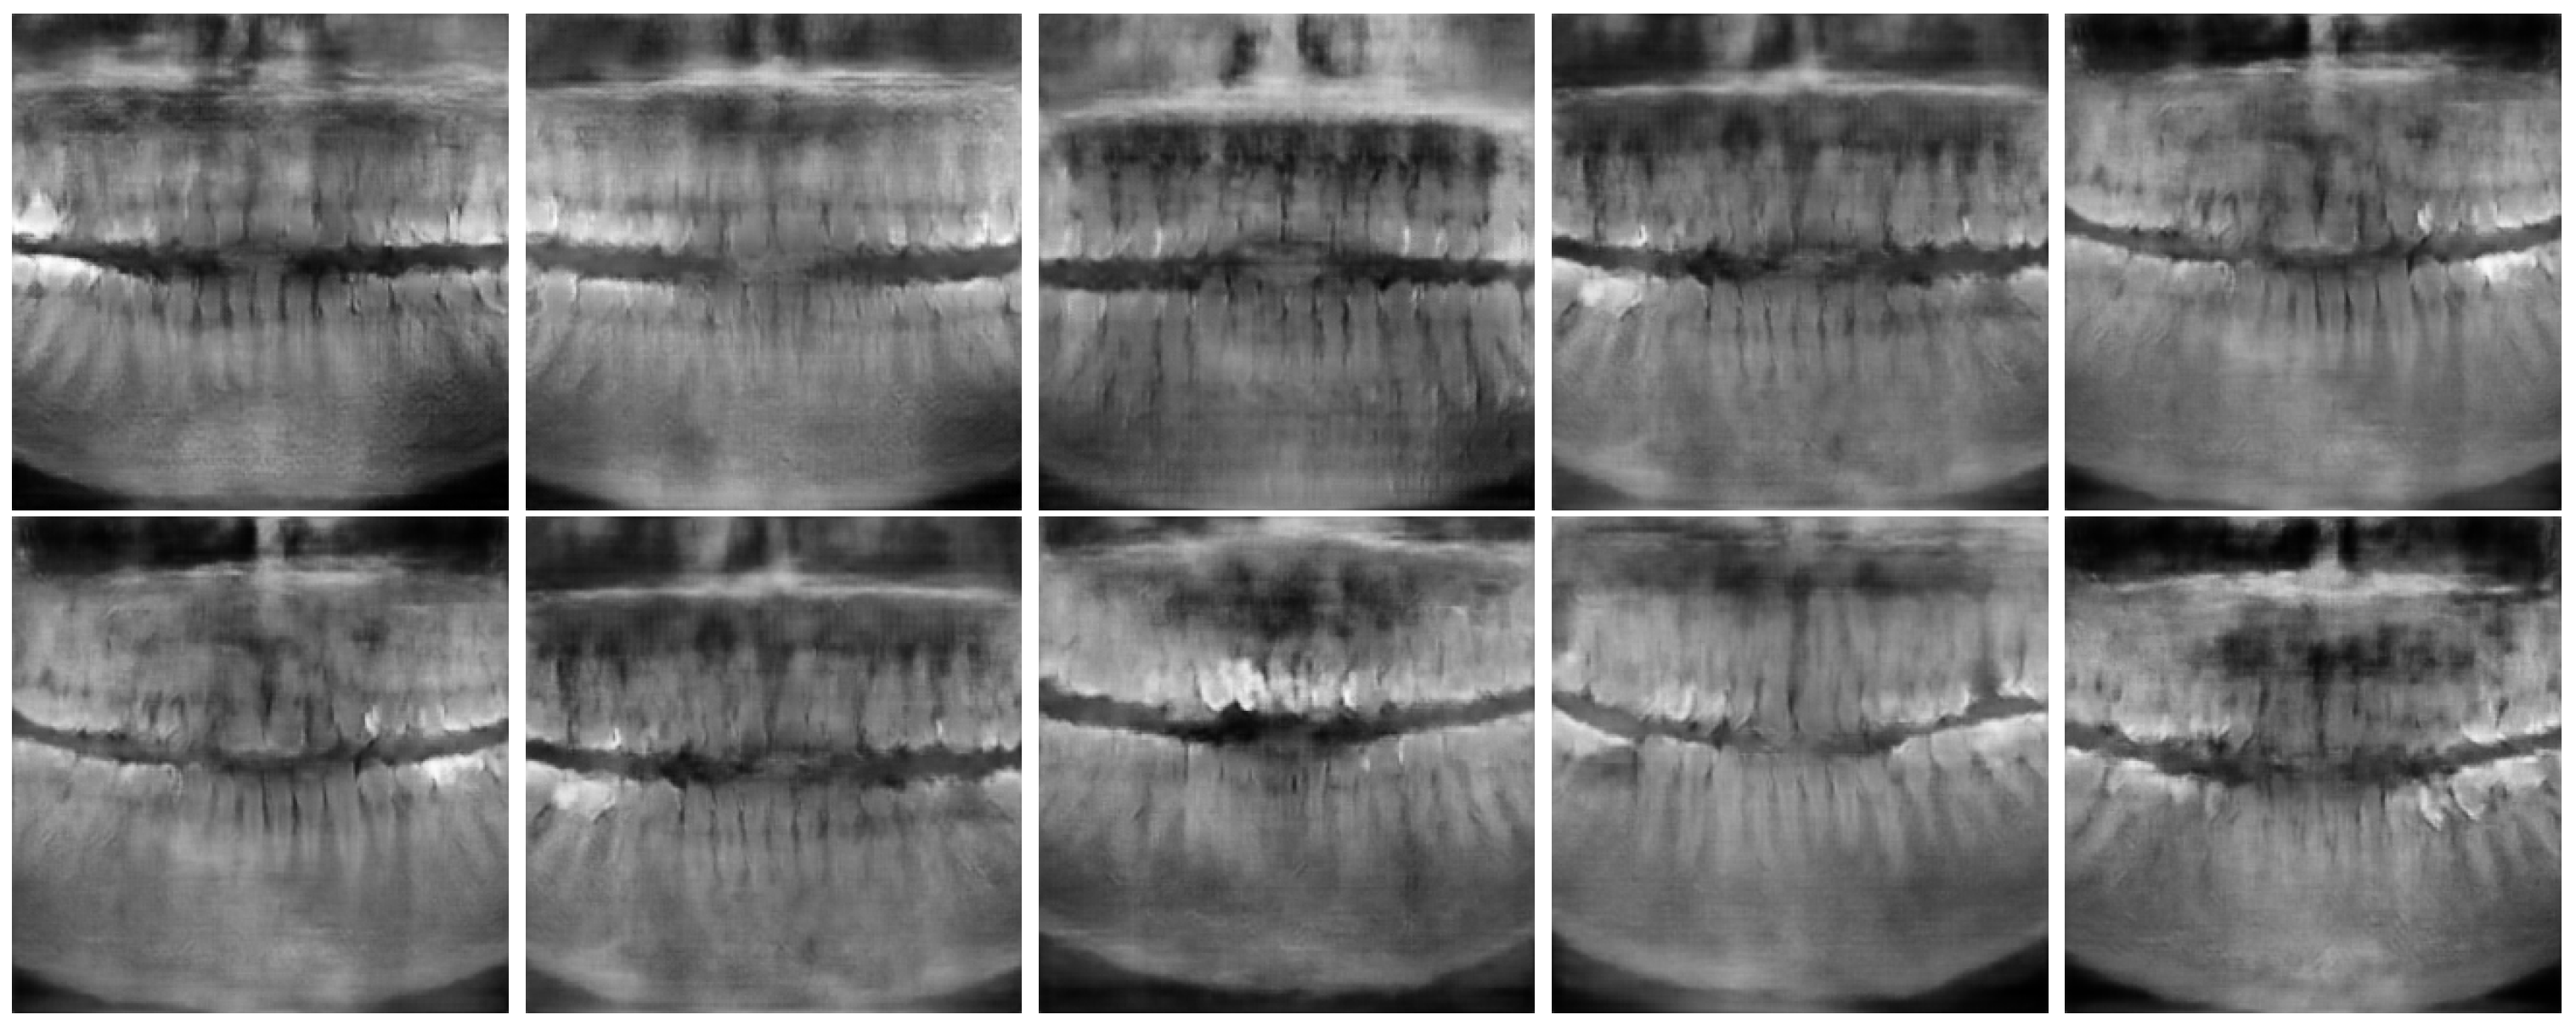

Figure 6 and Figure 7 show the best and worst generated images, respectively, as determined by the average scores for all twelve criteria. The best images show a reasonable depiction of both the overall morphology and certain details, although not at the level of contemporary real-world panoramic radiographs. The worst images display various issues, including poor overall image quality and manifestations of extra rows of tooth crowns.

Figure 6.

Best images generated using Models 1 (top row) and 2 (bottom row).